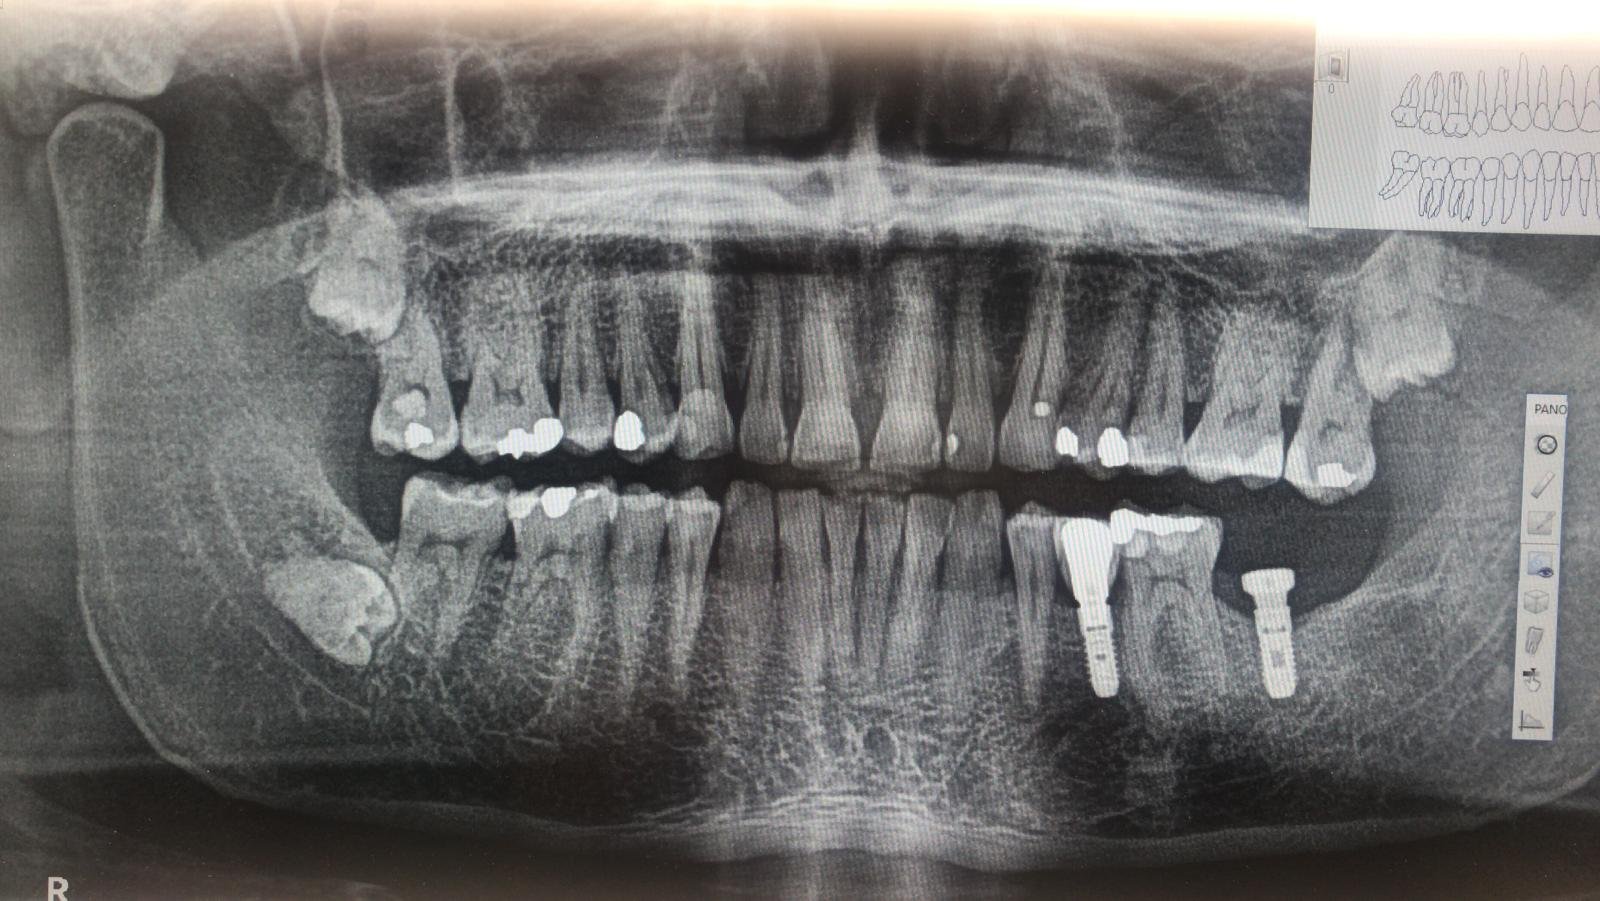

Implantes colocados hace unos años en idental. Me gustaría que me ayudarán a identificarlos